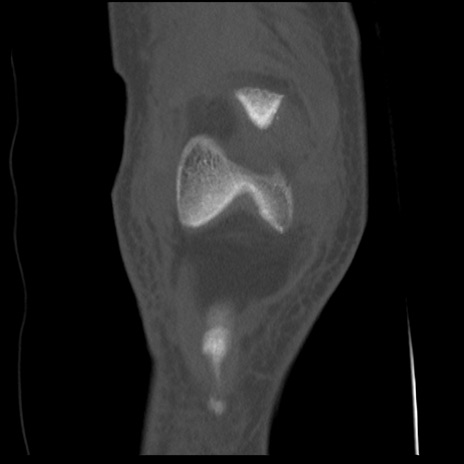

右膝関節CT

矢状断像